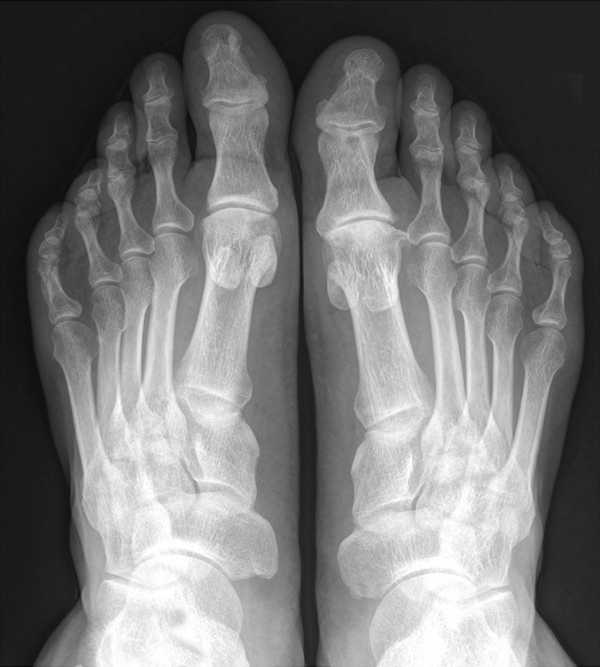

После осмотра врач обязательно назначает дополнительные исследования, к которым можно отнести:

- рентгенографию нижних конечностей в трех проекциях;

- плантографию, в ходе которой устанавливает не только стадия болезни, но и уровень нагрузки на ноги;

- подометрию (определение давления на стопы).

- Рентгенография в трех проекциях для определения патологических изменений в стопе.

- Компьютерная плантография показывает равномерность нагрузки на стопу.

- Компьютерная подометрия назначается для выявления бурсита на ранних стадиях.